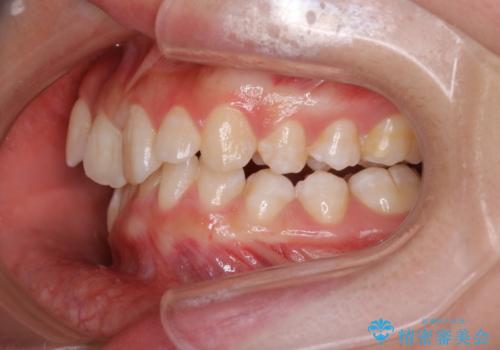

- 20代女性

- 1年9ヶ月

- 前歯のガタガタを主訴に来院されました。

抜歯を行い、インビザラインにて治療を完了しております。